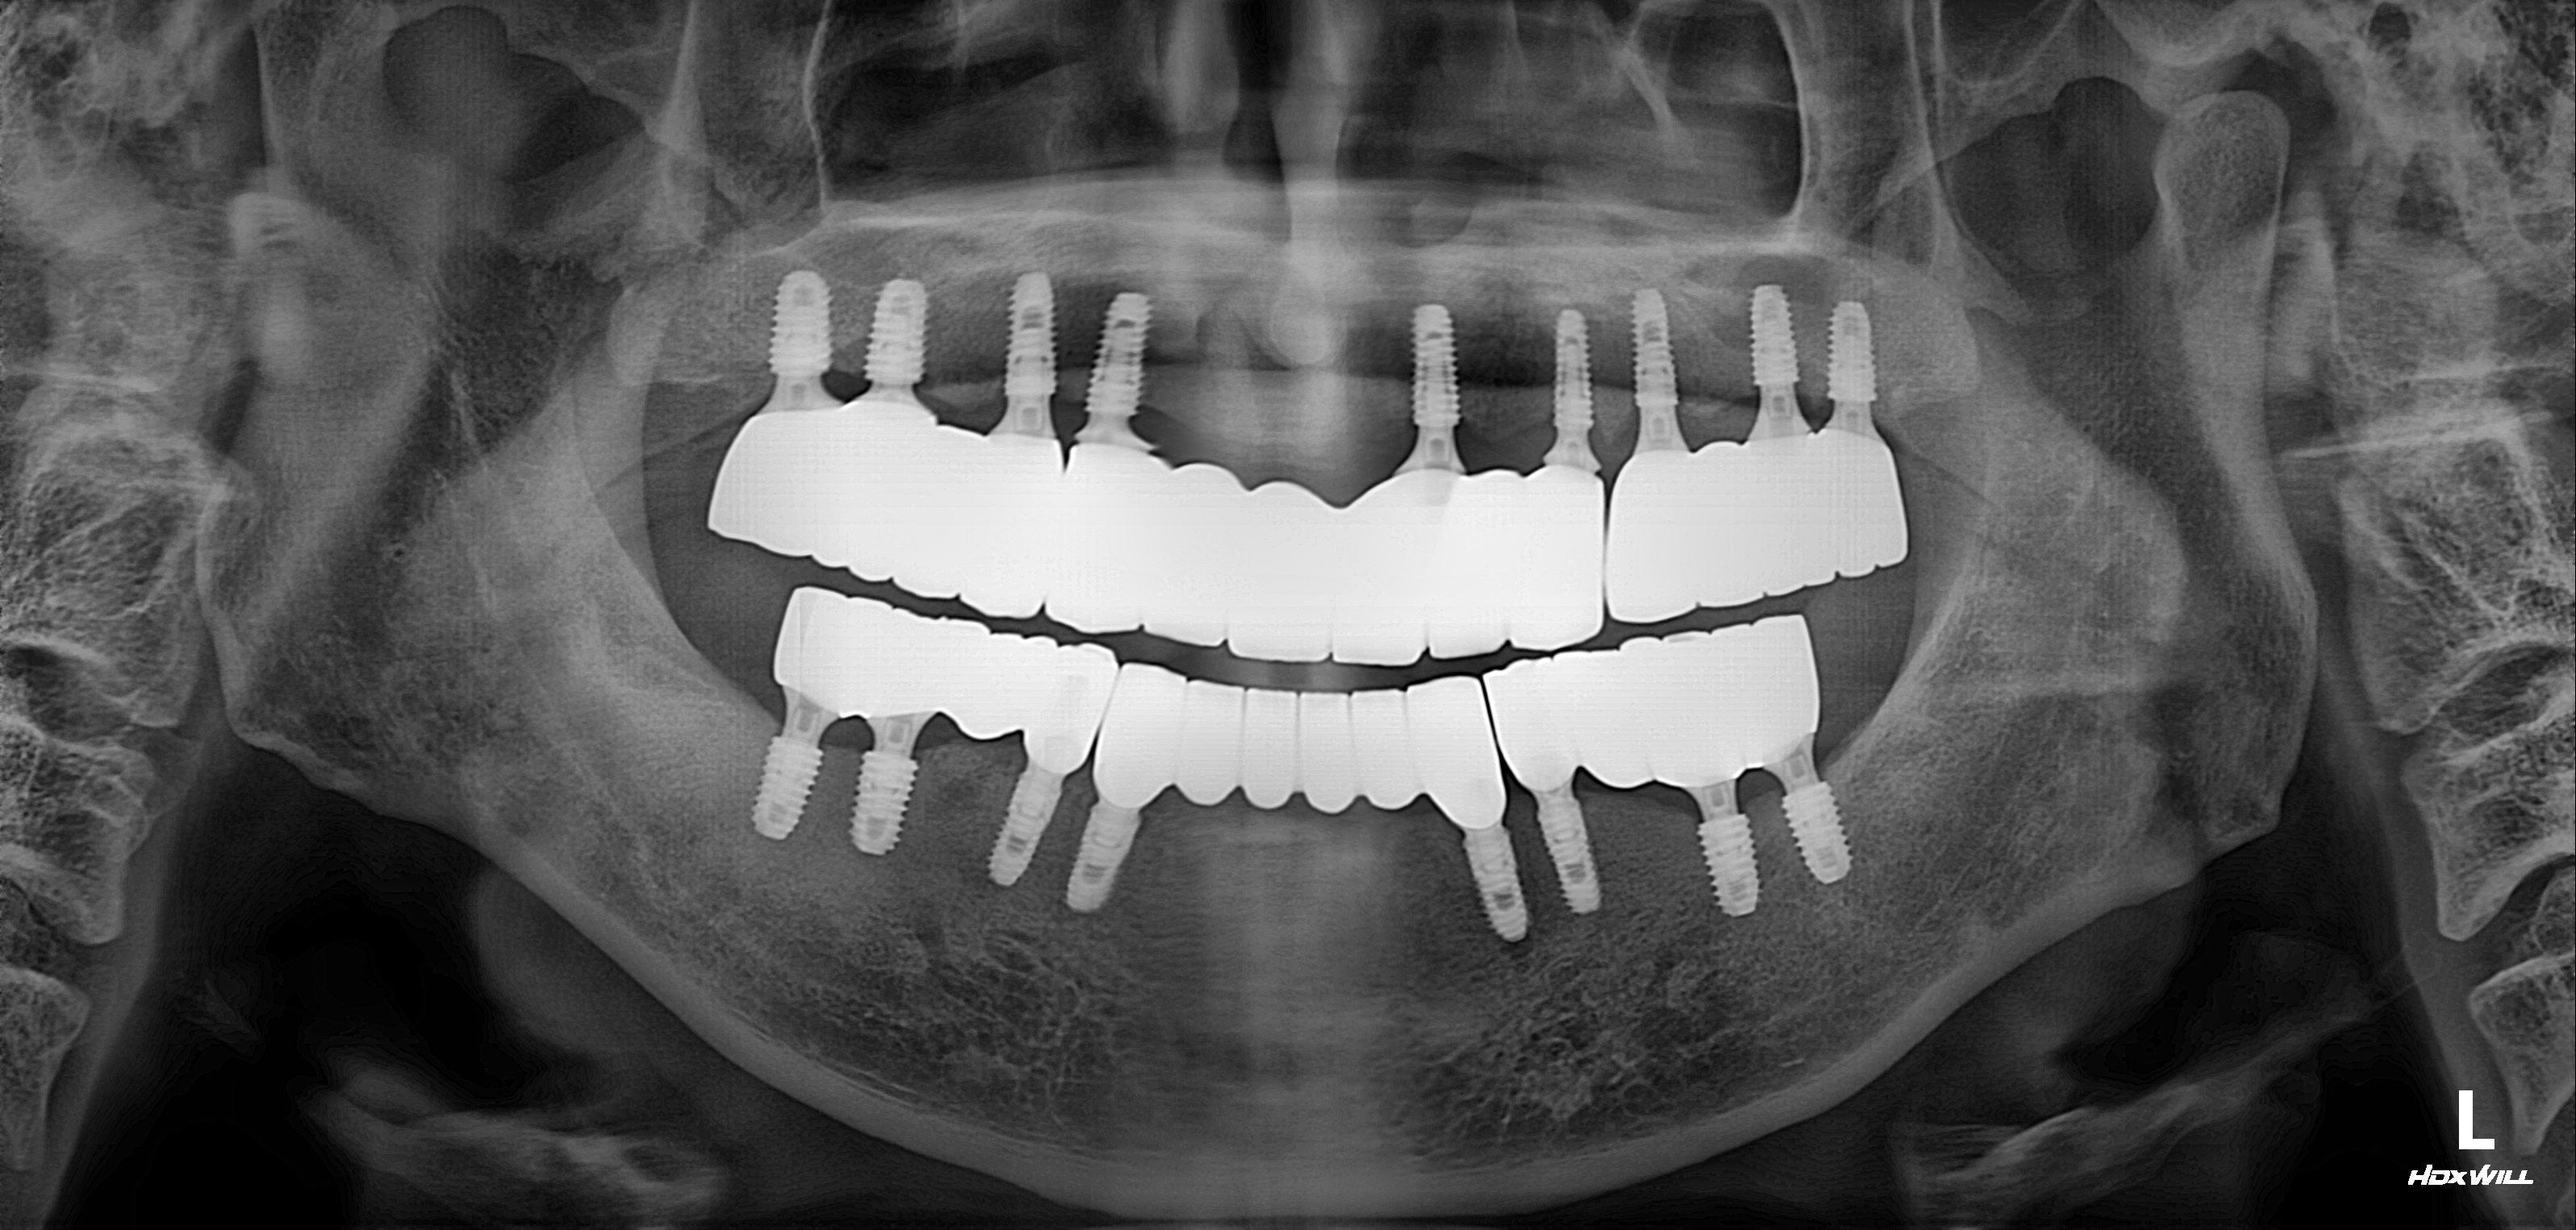

수술 전

수술 후

전악 임플란트 사례

전후사진